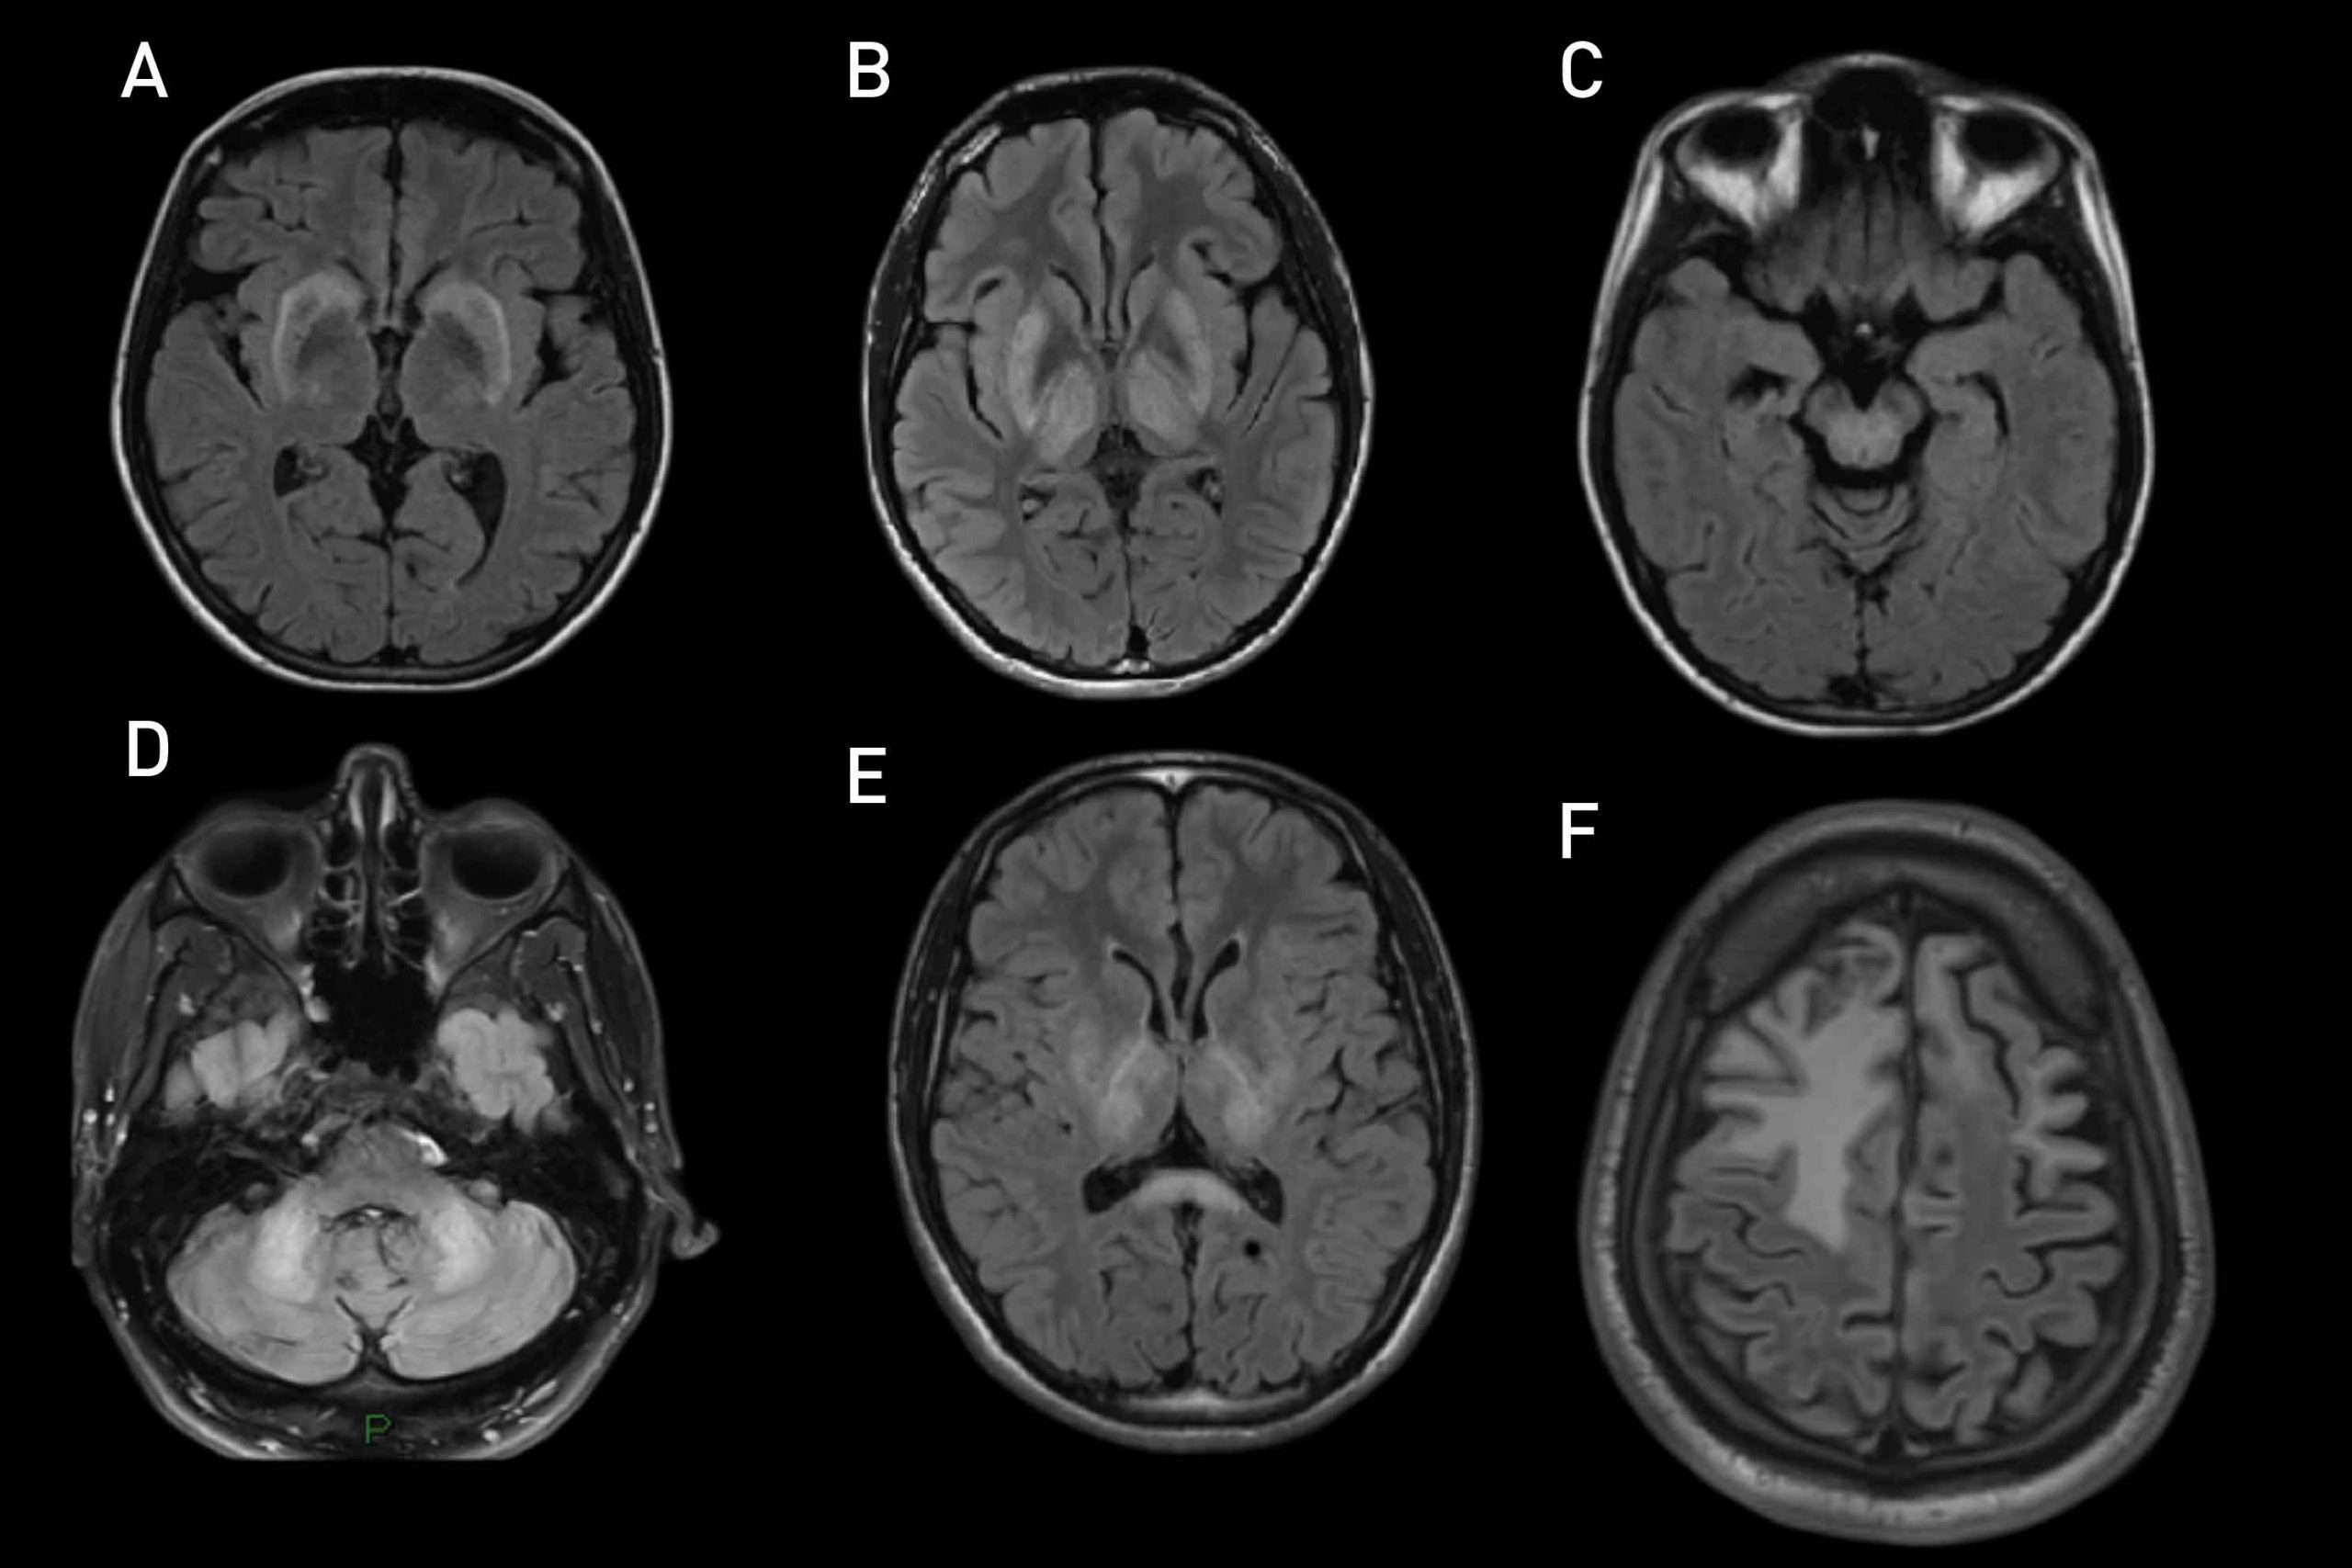

La Maladie de Wilson actualités Neurologies Maladie Wilson Forum the wilson disease association support community connects patients, families, friends and caregivers. Also known as hepatolenticular degeneration) was first described in 1912 by kinnear wilson as. wilson disease is a disorder of copper metabolism that, when untreated, can present with hepatic, neurologic, or. i'm here to learn more about wilson's disease from anyone who is more experienced. Maladie Wilson Forum.